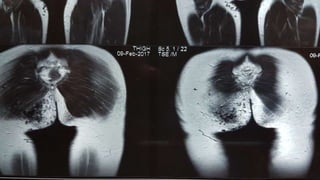

MRI

A LARGE 11.7x10.8x5.9cm AVM

IN RIGHT GLUTEAL REGION

THE LESION IS EXTENDING TO

THE ISCHIORECTAL AND

PERIANAL SPACE WITHOUT ANY

EXTENSION TO THE

INTERSPHINCTERIC REGION

FEEDING FROM BRANCHES OF

RIGHT INTERNAL ILIAC ARTERY

AND DRAINING INTO INTERNAL

ILIAC VEIN

RADIOLOGICAL INVESTIGATIONS USG ARTERIOVENOUS MALFORMATION INTHE RIGHT GLUTEAL MUSCLES MRI A LARGE 11.7x10.8x5.9cm AVM IN RIGHT GLUTEAL REGION THE LESION IS EXTENDING TO THE ISCHIORECTAL AND PERIANAL SPACE WITHOUT ANY EXTENSION TO THE INTERSPHINCTERIC REGION FEEDING FROM BRANCHES OF RIGHT INTERNAL ILIAC ARTERY AND DRAINING INTO INTERNAL ILIAC VEIN